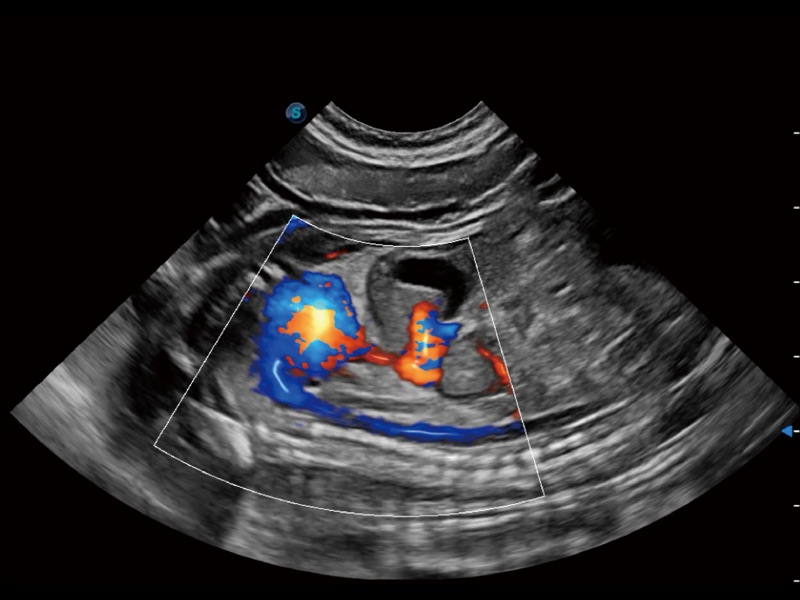

能够基于左心室壁追踪和辛普森法,自动计算射血分数,支持多个可移动点描迹,与手动测量相比,极大节省了动物医生的时间和精力。

通过360度任意调节3条M型取样线,在同一心动周期上观察心脏不同位置的运动曲线,得到准确的心功能测量数据,有效评估心肌运动及左心室功能。

实时用颜色表示心肌组织运动,观察和定量组织的运动情况,对快速检测与评估心肌的灌注和活性、电传导及心肌收缩和舒张功能等均能提供重要的诊断信息。